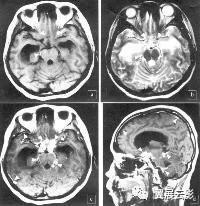

单纯疱疹病毒性脑炎

本病是单纯疱疹病毒侵入脑内引起的炎性脑炎,主要病理改变为脑实质内出血性坏死及神经元和神经胶质细胞核内有病毒包涵体存在,本病发病通常无季节性,散在发生,发病急,病情严重,主要受累部位为额叶,岛叶,额叶皮质下区和扣带回,脑干和脑神经亦可受损,主要临床表现为发热,头疼,恶心,呕吐,脑膜刺激征,重症可出现抽搐,精神症状及意识障碍。

MR平扫于双侧或单侧颞叶,扣带回,岛叶等部位见片状长T1长T2异常信号,合并出血时其内可见点状或小斑片状短T1信号,局部脑组织肿胀,增强扫描病灶区可见斑片状或脑回状强化。本病在发病部位上具有一定特征,因此应详细描写病变所累及的脑叶,描写病变信号时应注意是否合并出血,结合临床表现本病一般诊断不难。